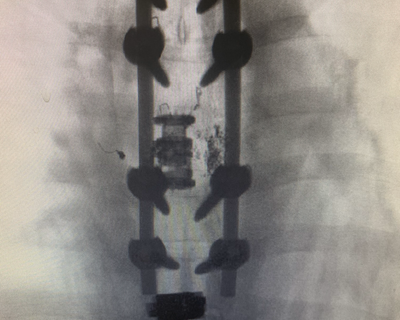

The day after the C-section, a neurological surgeon would perform what’s known as a vertebral corpectomy and fusion. He would remove the section of vertebrae which held the hemangioma and insert titanium screws and rods to stabilize the area long-term.

The following day, the neurological surgeon completed Carla’s hemangioma removal in about three hours. Carla doesn’t remember much of either day because of the anesthesia and pain medication. She was so disoriented following back surgery, she asked Andrew, “Have I been in a car accident?” The pain from the C-section “felt like a paper cut” compared to the back surgery, she said. Andrew spent the next three days shuttling back and forth between Elodie in the NICU and Carla in the ICU, sharing photos of their baby with his wife. She couldn’t wait to spend time with Elodie.